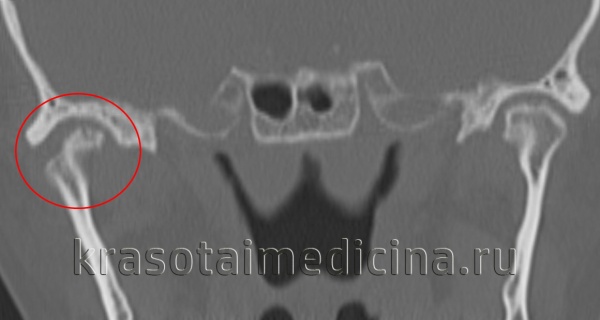

Проведены МРТ ВНЧС, по данным которой определяется полная вентральная дислокация обоих дисков ВНЧС без репозиции, и конусно-лучевая компьютерная томография (КЛКТ) лицевого скелета, обнаружившая наличие асимметричной скелетной деформации за счет уменьшения задней лицевой высоты и размеров обоих мыщелковых отростков. С целью определения дальнейшей тактики ведения пациентки и проведения комплексного лечения имеющихся хронического болевого синдрома и деформации лицевого скелета консультирована совместно челюстно-лицевым хирургом, ортодонтом и неврологом, а в последующем, после обнаружения высоких титров вируса герпеса человека 6-го типа (ВГЧ-6) в крови и слюне, направлена к дерматовенерологу в Герпетический центр. Диагностированы дисфункция ВНЧС, асимметричная деформация лицевого скелета с тенденцией к вертикальному типу роста, мигрень без ауры, постгерпетическая нейропатия II ветви правого тройничного нерва (ВГЧ-6).

КТ ВНЧС. Артроз правого височно-нижнечелюстного сустава: деформация мыщелка нижней челюсти, сужение суставной «щели», остеофиты.